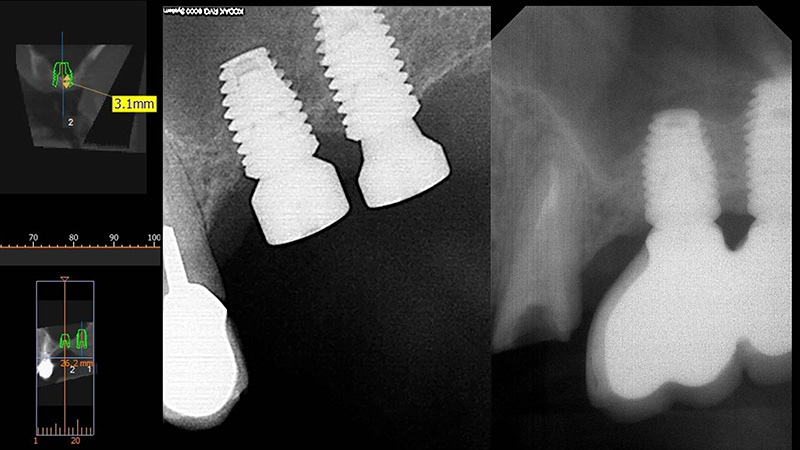

CBCT avant et après la pose combinée au comblement et à l’élévation du plancher sinusien.